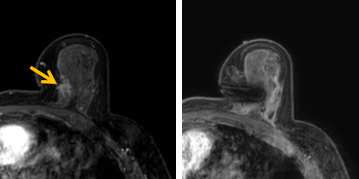

患者李女士磁共振檢查發(fā)現(xiàn)右乳內(nèi)側(cè)高度可疑病變,病變小摸不到,超聲和X線攝影(鉬靶)都看不到,怎么辦?要想明確病變性質(zhì),必須進(jìn)行磁共振引導(dǎo)下精準(zhǔn)足量的活檢,但是這種技術(shù)操作難度大、軟硬件要求高。

經(jīng)過仔細(xì)查體并分析所有影像資料,陳寶瑩發(fā)現(xiàn),病變靠近胸大肌,容易造成術(shù)中損傷?;颊呷榉枯^小,病變?cè)趦?nèi)側(cè),導(dǎo)致乳房不易固定,進(jìn)針難度大,與患者充分溝通后,陳寶瑩帶領(lǐng)團(tuán)隊(duì),制定了細(xì)致的操作方案,術(shù)中,醫(yī)護(hù)團(tuán)隊(duì)反復(fù)調(diào)整體位和固定架的角度及方向,利用隔離技術(shù)保護(hù)好周圍組織。受乳房形態(tài)和病變位置的限制,醫(yī)生只能蹲著、跪著進(jìn)行操作,經(jīng)過30多分鐘終于順利完成,精準(zhǔn)獲取了足量的組織,而且一針到位,創(chuàng)傷小、出血少,患者沒有任何不適,做完即回家休息。幾天后,病理證實(shí)是一種特殊類型的早期乳腺癌,為后續(xù)進(jìn)一步治療方案的制訂提供了準(zhǔn)確依據(jù)。